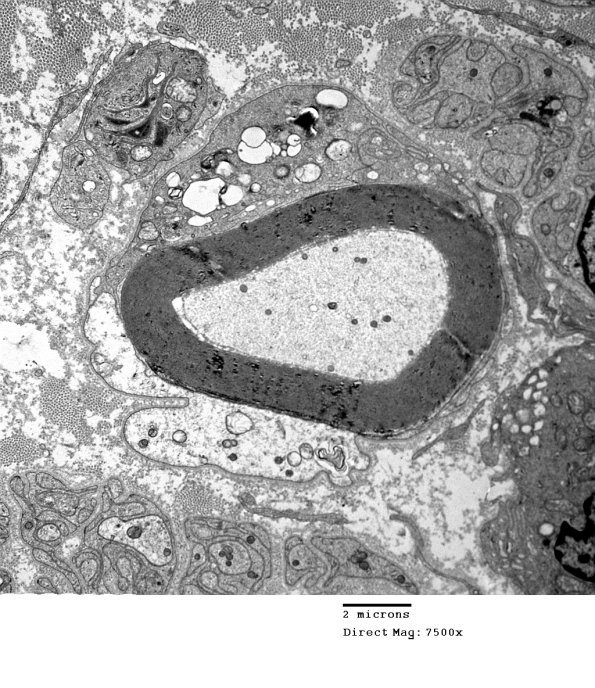

1D20A,B Additional images of macrophage mediated demyelination. (electron micrographs)